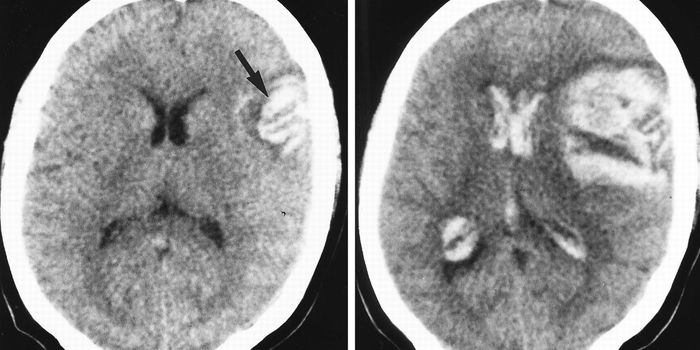

FEB 19, 2016CardiologyAt the recent International Stroke Conference of 2016, researchers presented a study that connected untreated high blood ...

AUG 10, 2017NeuroscienceMany kids love to splash and swim in a pool or at the beach, but all too often accidents can happen, especially with you ...